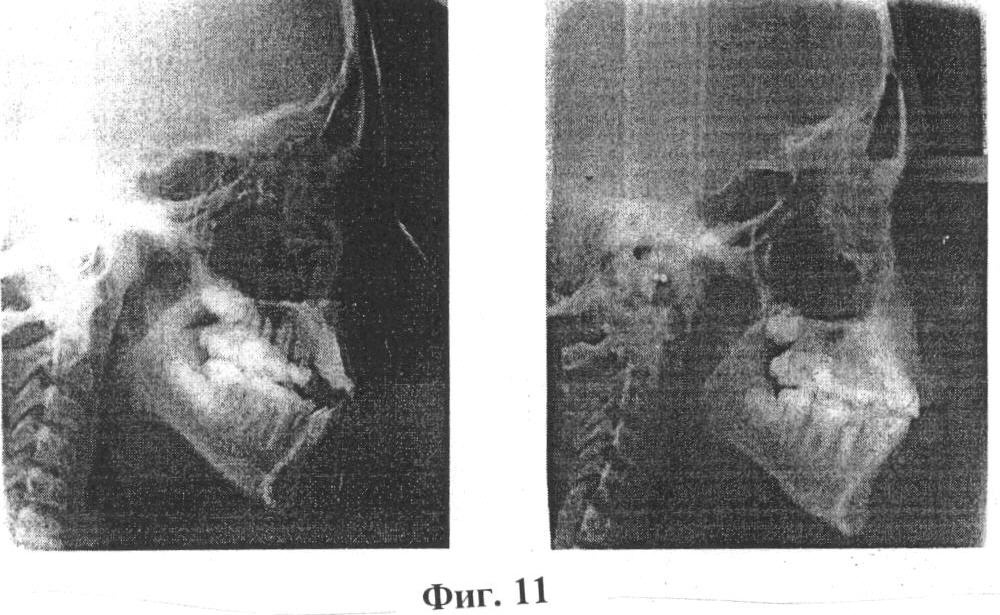

Изобретение иллюстрируется фотографиями, где на фиг.1 и 2 показаны зубные ряды верхней и нижней челюстей пациентки А., на фиг.3 – расположение несъемного аппарата с тремя направляющими на верхней челюсти для расширения и удлинения верхнего зубного ряда (стрелками указано направление активации винта), на фиг.4 показана реплантация клыка и премоляра, фиксация брекетов на эти зубы, шинирование в зубном ряду при помощи ортодонтической дуги и металлических лигатур, разобщение прикуса за счет окклюзионных накладок из стеклоиономерного цемента на 36 и 46 зубы, на фиг.5 показаны фотографии зубных рядов пациентки А. после ортодонтического лечения, на фиг.6 показана фиксация брекетов, колец и небного бюгеля на зубы верхней челюсти, на фиг.7 – зубные ряды пациентки А. верхней и нижней челюстей после ортодонтического лечения, на фиг.8 – ортопантомограмма пациентки А. до ортодонтического лечения, на фиг.9 – ортопантомограмма пациентки А. через 6 месяцев после реплантации клыка и премоляра, на фиг.10 – ортопантомограмма пациентки А. после ортодонтического лечения, на фиг.11 – телерентгенограммы пациентки А. до и после ортодонтического лечения, на фиг.12 и 13 – гипсовые модели пациентки А. до и после ортодонтического лечения соответственно.

После окончания активного ортодонтического лечения профиль и улыбка пациентки А. (14 лет 6 мес.) значительно улучшились (фиг.7). На верхнюю челюсть был изготовлен съемный ретейнер и несъемный на зубы нижней челюсти (фиг.8). Реплантированные зубы болезненных ощущений у пациентки А. не вызывали на протяжении всего курса ортодонтического лечения. При осмотре полости рта подвижности этих зубов не наблюдалось. Электроодонтодиагностика клыка после снятия брекетов была равна 13 мкА, премоляра – 19 мкА.

Нестандартность проведенного комплексного лечения состояла в применении брекет-системы и несъемного аппарата с тремя направляющими (винт Бертони) для расширения и удлинения верхнего зубного ряда и реплантации клыка и премоляра с использованием синтетического коллаген-апатитового материала «ЛитАр» для оптимизации репаративного остеогенеза. У данной пациентки проведена компьютерная томография верхней и нижней челюсти, ортопантомография и телерентгенография, изучение гипсовых моделей челюстей до и после ортодонтического лечения (фиг. 9, 10, 11, 12, 13, 14).